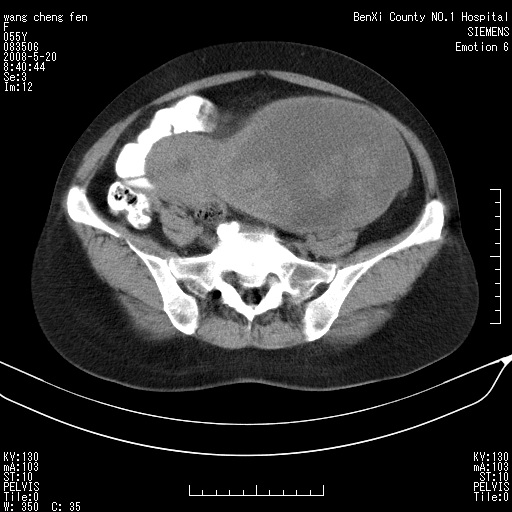

女、绝经后阴道流血3个月

左侧附件区可见一囊性占位,边缘清楚,内可见不规则形软组织影 ce:囊壁及内部可见强化 考虑 卵巢囊腺瘤

左侧附件区巨大囊实性病灶,边缘光整,病灶囊壁较厚,增强示囊壁及实性部分明显强化,强化呈度与宫体实质大致相同,宫腔积液征像,未见盆腔积液等其他异常,考虑左侧卵巢囊腺癌,不除外囊腺瘤及浆膜下肌瘤坏死

左侧附件区巨大囊实性病灶,边缘光整,病灶囊壁较厚,增强示囊壁及实性部分明显强化,强化呈度与宫体实质大致相同,宫腔积液征像,未见盆腔积液等其他异常。绝经后阴道流血3个月,结合病史左侧卵巢囊腺癌首先考虑,宫腔扩大不除外累及。期待结果。

支持浆膜下子宫肌瘤.之前由于网络原因未看全图片,现在重看,宫颈见一类圆形低密度影,增强轻度强化,低于肌层强化,宫腔扩大,考虑宫颈癌伴宫腔积液可能性大.

囊实性肿块分隔厚度较大,厚薄不均,增强实性成分明显强化,有不规则阴道流血,卵巢囊腺癌可能性大。

1,宫颈部占位,宫颈癌?2,左侧附件区囊实性占位,界较清,实质部分强化明显。考虑浆膜下或阔韧带肌瘤囊变可能大。囊腺类肿瘤不除外。